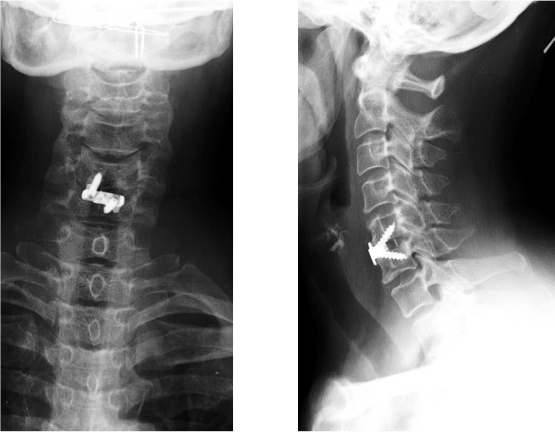

Figure 3. Clichés postopératoires après discectomie et mise en place d'une cage cervicale d'arthrodèse.

Une fois le disque retiré, on positionne entre les 2 corps vertébraux une cage remplie d'os ou d'un substitut osseux. Une cage est un dispositif médical implantable en plastique qui permet de maintenir l'espace entre les 2 corps vertébraux ; elle peut être fixée à l'os par des vis ou des agrafes. Elle maintient les vertèbres en attendant que la fusion soit acquise (3 à 6 mois en moyenne) (Figures 2 et 3).